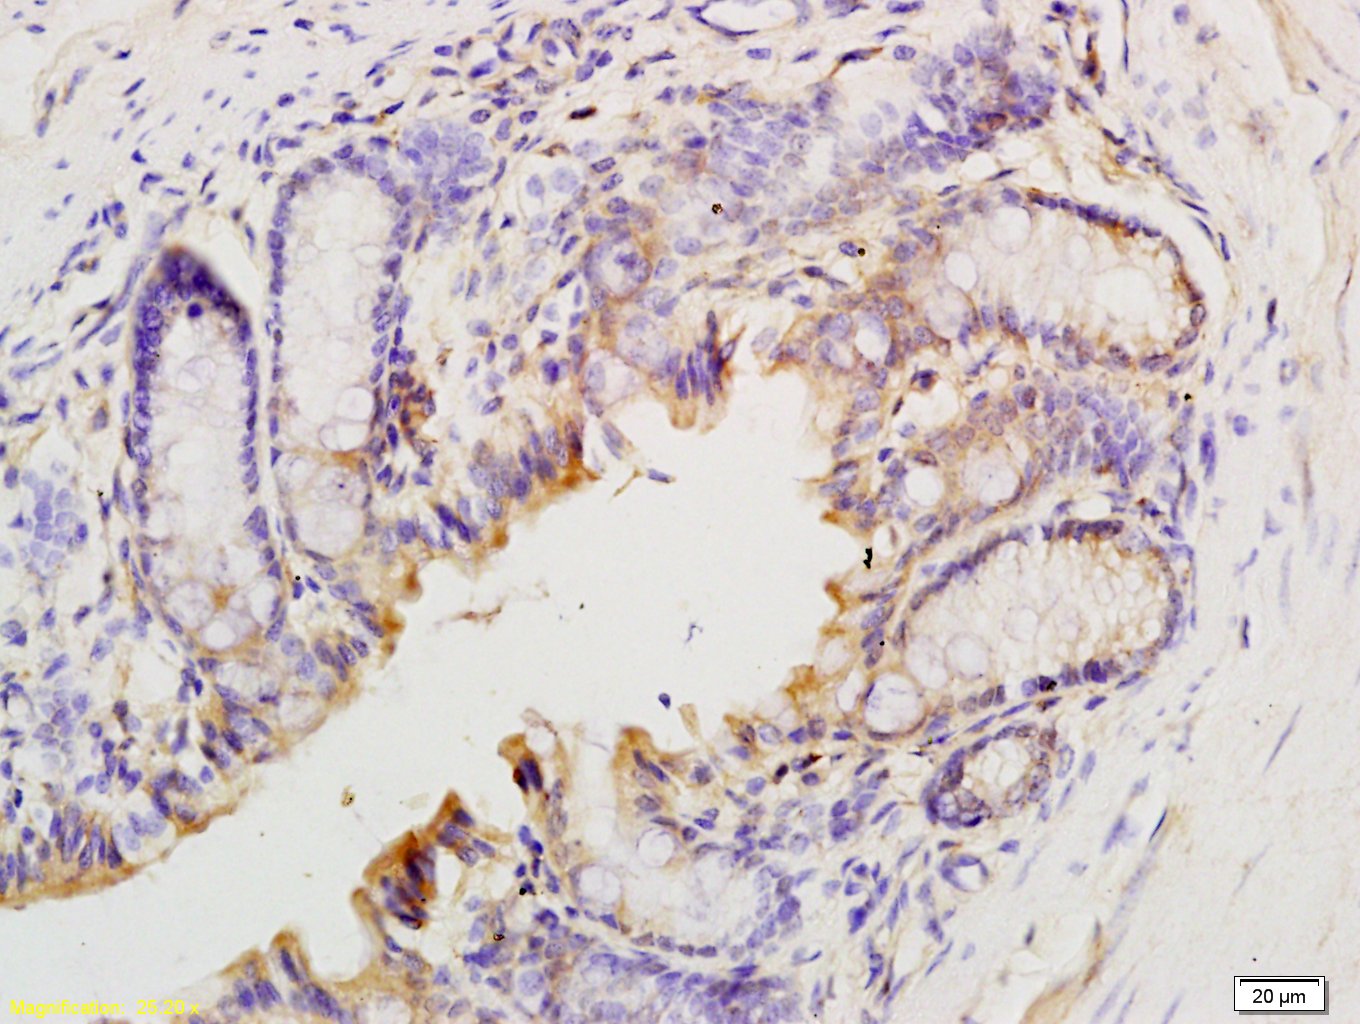

| 英文名称 | T Beta 10 Rabbit pAb |

| 中文名称 | 胸腺素β10抗体 |

| 产品应用 | IHC-P=1:100-500, IHC-F=1:100-500, IF=1:100-500 Not yet tested in other applications. |

Antigen retrieval: citrate buffer ( 0.01M, pH 6.0 ), Boiling bathing for 15min; Block endogenous peroxidase by 3% Hydrogen peroxide for 30min; Blocking buffer (normal goat serum,C-0005) at 37℃ for 20 min;

Incubation: Anti-T-Beta-10 Polyclonal Antibody, Unconjugated(bs-R) 1:200, overnight at 4°C, followed by conjugation to the secondary antibody(SP-0023) and DAB(C-0010) staining